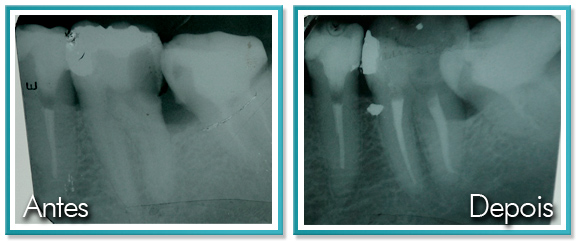

7. ESPAÇO ENTRE OS DENTES

O Espaço entre os dentes te incomoda?

Veja a seguir como resolver este problema de forma rápida e eficaz.

O fechamento de diastema (espaço) entre os dentes inferiores com planejamento para colocação de implante.

Logo abaixo, a foto da última consulta antes do remoção do aparelho, já com o espaço fechado.

O tratamento foi realizado em 1 ano.